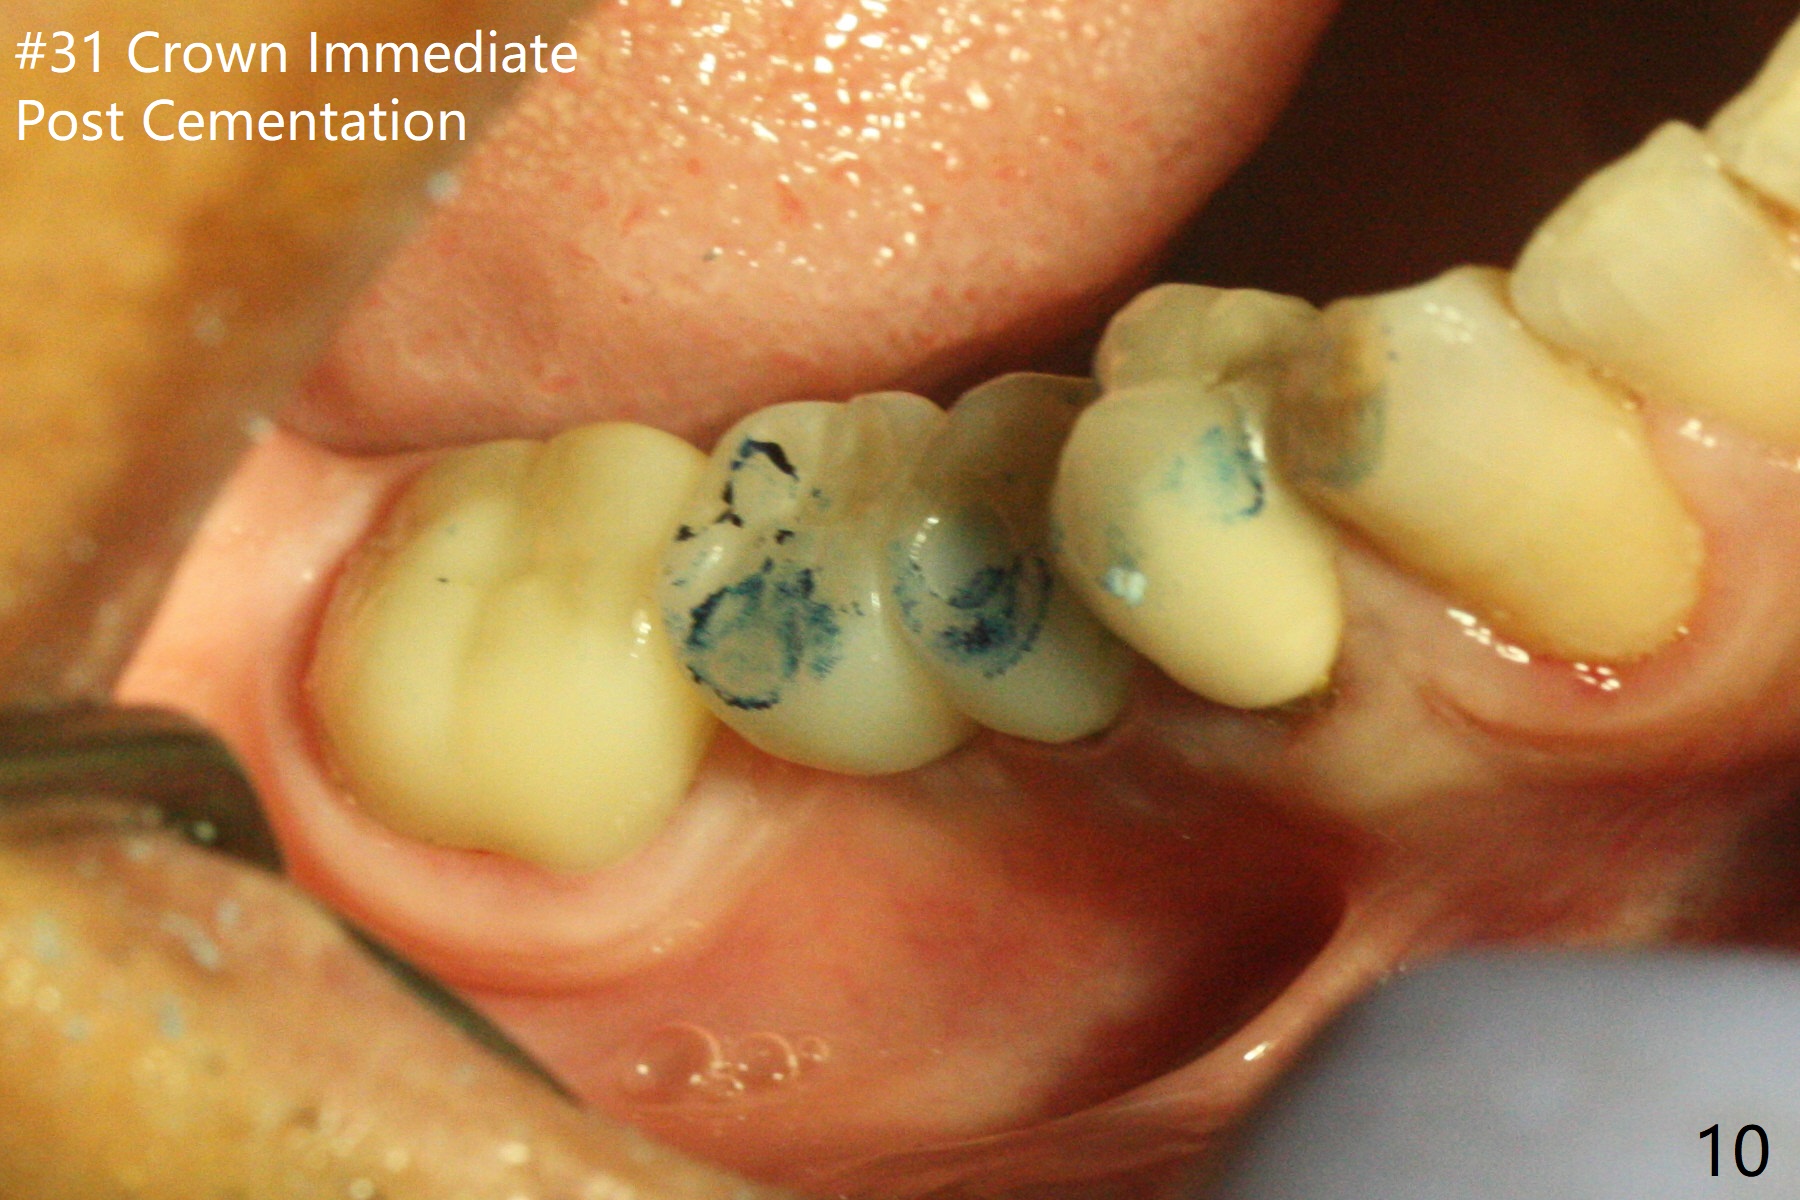

Preop examination shows that the buccal plate at #30 is atrophic (Fig.1 *). The mesiodistal width of the pontic is narrow as compared to the retainer at #31 (Fig.2). It appears that a narrow implant should be placed at #30 and should be able to sustain functional loading. After ridge reduction at #30 (Fig.3 ^) and extraction and debridement at #29, osteotomies at these sites are initiated with 1.2 mm and 2 mm drills, respectively. Probably due to low bone density, the osteotomy at #29 drops deep and close the Mental Loop (red dashed line). While the trajectory at #30 improves, the osteotomy at #29 remains close to the Mental Loop (Fig.4), asymptomatic with infiltration anesthesia. A 3x12(2) mm 1-piece implant is placed at #30 and 3.8x16 mm 2-piece implant at #29 (Fig.5,6 with insertion torque >50 and <50 Ncm, respectively). The large distal defect at #29 (Fig.3,5 *, most likely due to post-related perforation) is later filled with bone graft (data not shown). After placing an abutment at #29 and suturing, periodontal dressing is applied. Three months later, the meisal gap of #29 disappears while the distal one reduces (Fig.7 *). The abutment is changed to 4.5x4(4) mm one before reprep for impression. There is no bone loss 9 months post cementation (Fig.8) or 3 years 9 months post cementation (Fig.9). In fact the crown is lost at #31. At repeated request from the patient, a prefabricated post and crown will be fabricated for short term purpose while an implant is going to be placed at #19. The new crown at #31 has no occlusal contact (Fig.10), which may change over time.